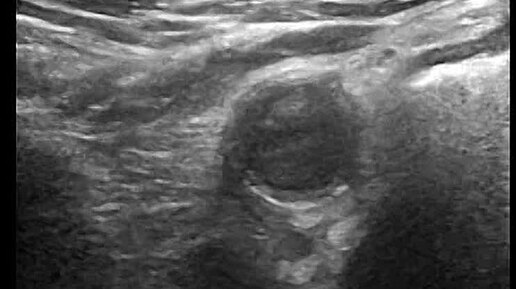

Видео к статье ОСТРЫЙ АППЕНДИЦИТ. ВИЗУАЛИЗАЦИЯ НА ВСЁМ ПРОТЯЖЕНИИ. Адрес: https://dzen.ru/a/aSQThYhcViklloR6